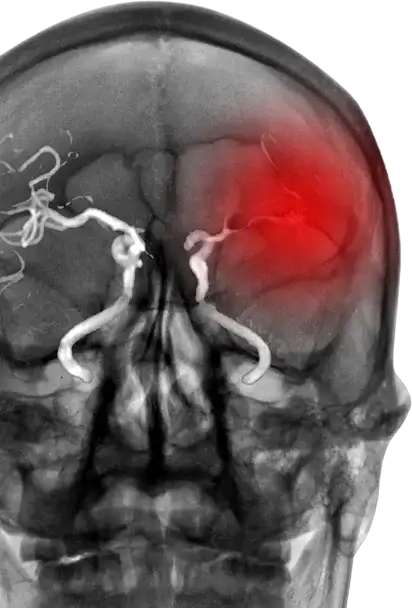

Position matters

Toro 88 enables physicians to confidently reach further. Patients with large bore catheters located in the petrous segment or beyond have a significantly higher first-pass effect and shorter procedure times.*

Higher intracranial positioning of an 8F guide catheter improves efficacy of aspiration thrombectomy in large vessel occlusions.

*Daryl Goldman 1 , Preethi Reddi 2 , Mais Al-Kawaz 3 , Kurt A Yaeger 2 , Trevor Hardigan 2 , Amol Mehta 2 , Jacopo Scaggiante Affiliations expand

PMID: 39299745 PMCID: PMC12171490 DOI: 10.1136/jnis-2024-022026

Position matters Featured Image